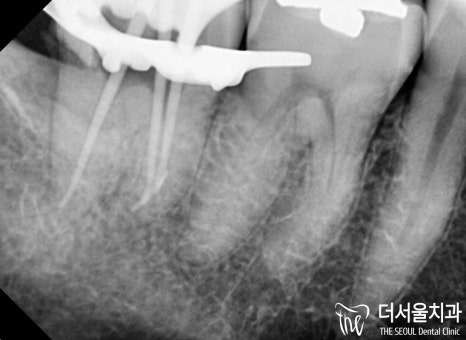

이후 본격적으로 근관치료 과정을 진행했습니다.

감염된 근관을 제거한 다음

확장을 통해 좁아져 있는 곳을 넓혀줍니다.

이후 약제를 투입하여 병소를 제거하고

치과용 수복재를 뿌리 끝까지 채워 넣으면 되죠.

core 작업